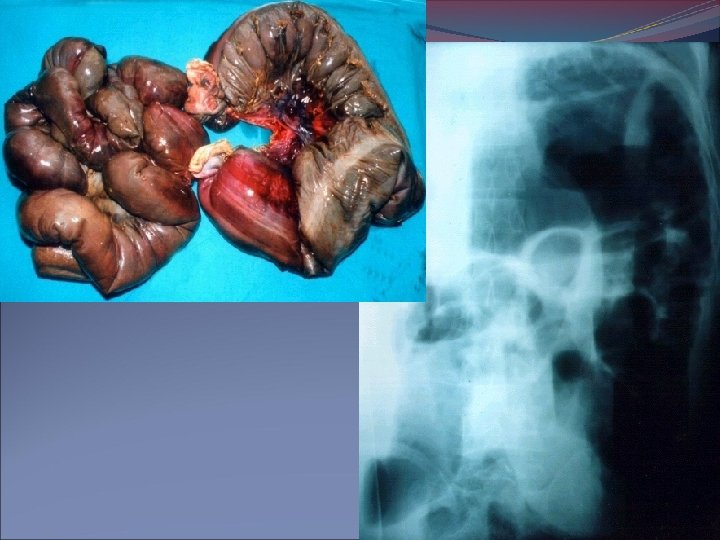

Signos de huellas digitales, pérdida del patrón mucoso, gas dentro de la pared intestinal o ramas intrahepáticas de la vena porta estrangulación de la obstrucción. Placa en bipedestación o en decúbito lateral, aire libre intraperitoneal perforación intestinal. Íleo paralítico distensión gaseosa de distribución uniforme en estómago, ID. y colon.

IMAGENOLOGÍA Radiografía de abdomen simple: Sigmoides distendido en forma de U invertido o grano de café

Radiografía de obstrucción del intestino delgado Íleo: Radiografía de la distensión intestinal

VÓLVULO: Segmento de intestino delgado con una zona de torsión.